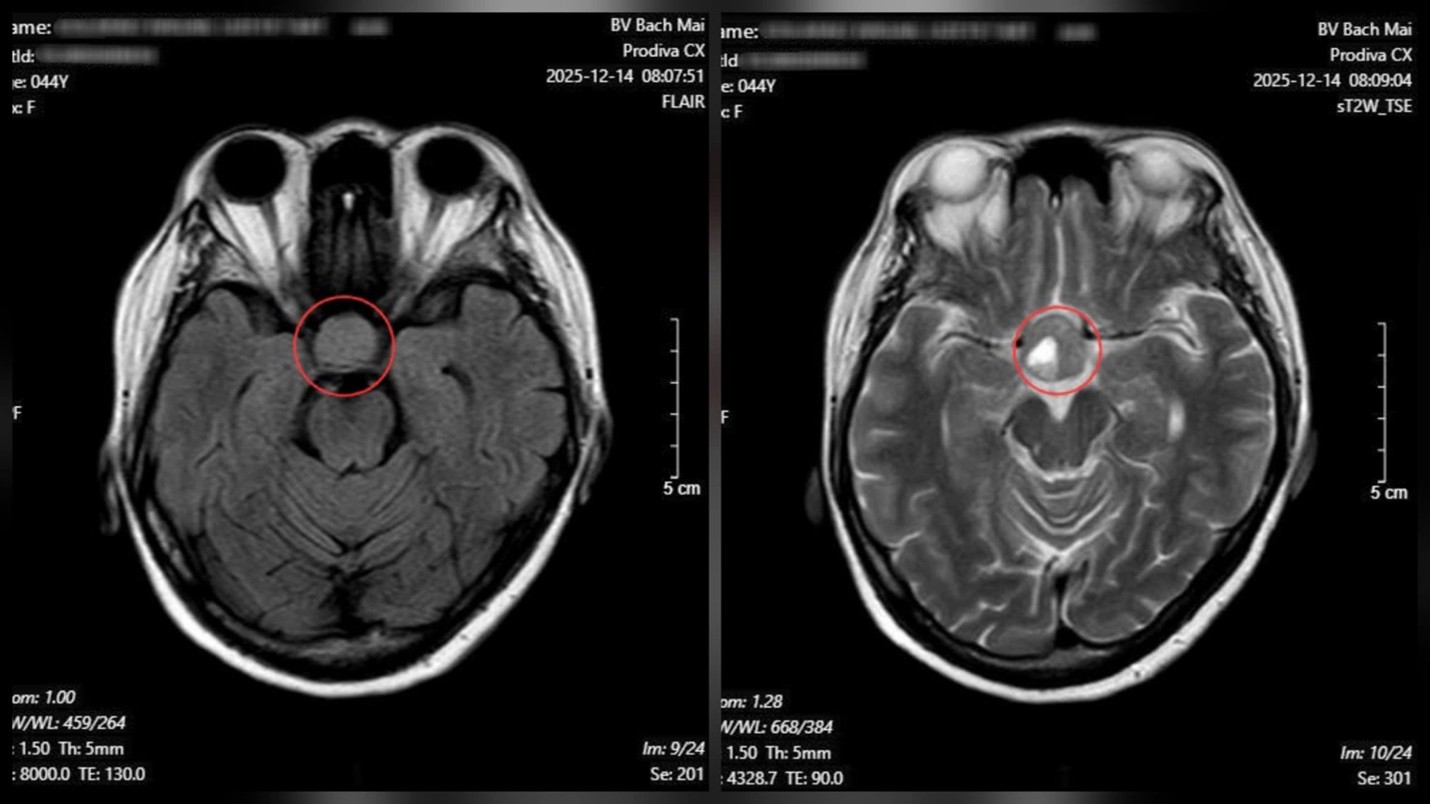

Từ những dấu hiệu trên, bệnh nhân được chỉ định chụp cộng hưởng từ (MRI) sọ não. Kết quả cho thấy một khối u tuyến yên kích thước lớn (macroadenoma), kích thước 26 × 21 mm.

Kết quả chụp cộng hưởng từ (MRI) sọ não cho thấy một khối u tuyến yên kích thước lớn